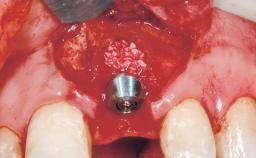

Early Placement of an Implant in a Maxillary Right Central Incisor Site

This 41-year-old female patient was referred to the clinic for the replacement of the right central incisor, since the tooth had developed a root fracture in the long axis that made extraction necessary. The healthy, non-smoking patient was first seen with the tooth still in place. A detailed Esthetic Risk Assessment was performed.The patient was worried about her dental esthetics and had high expectations for a successful treatment outcome from an esthetic point of view. The patient had a medium lip line that displayed parts of the gingiva in the anterior maxilla upon smile.

Bone Augmentation Horizontal|Simultaneous

Augmentation Materials Autogenous chips|Xenogenous|Membrane

Bone Volume Deficient horizontally, allowing simultaneous augumentation